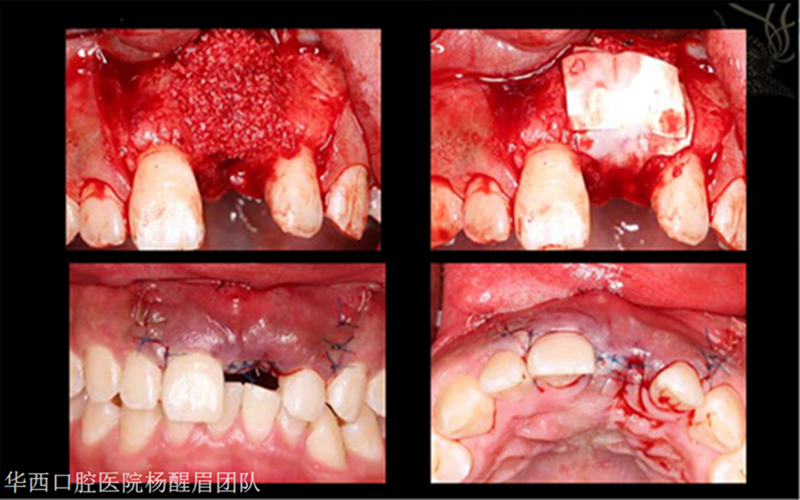

1.完成導航手術(shù)器械準備工作 2.軟組織翻瓣,充分暴露解剖形態(tài)

根據(jù)術(shù)前設(shè)計的種植方案開展手術(shù)

1.逐級備洞 2.術(shù)中,導航對種植區(qū)域位點,角度及深度實時引導 3.根據(jù)導航方案完成擴孔工作

植入種植體,根據(jù)術(shù)前方案,植體位點偏舌側(cè)

1.同期GBR植骨粉骨膜 2.進行縫合